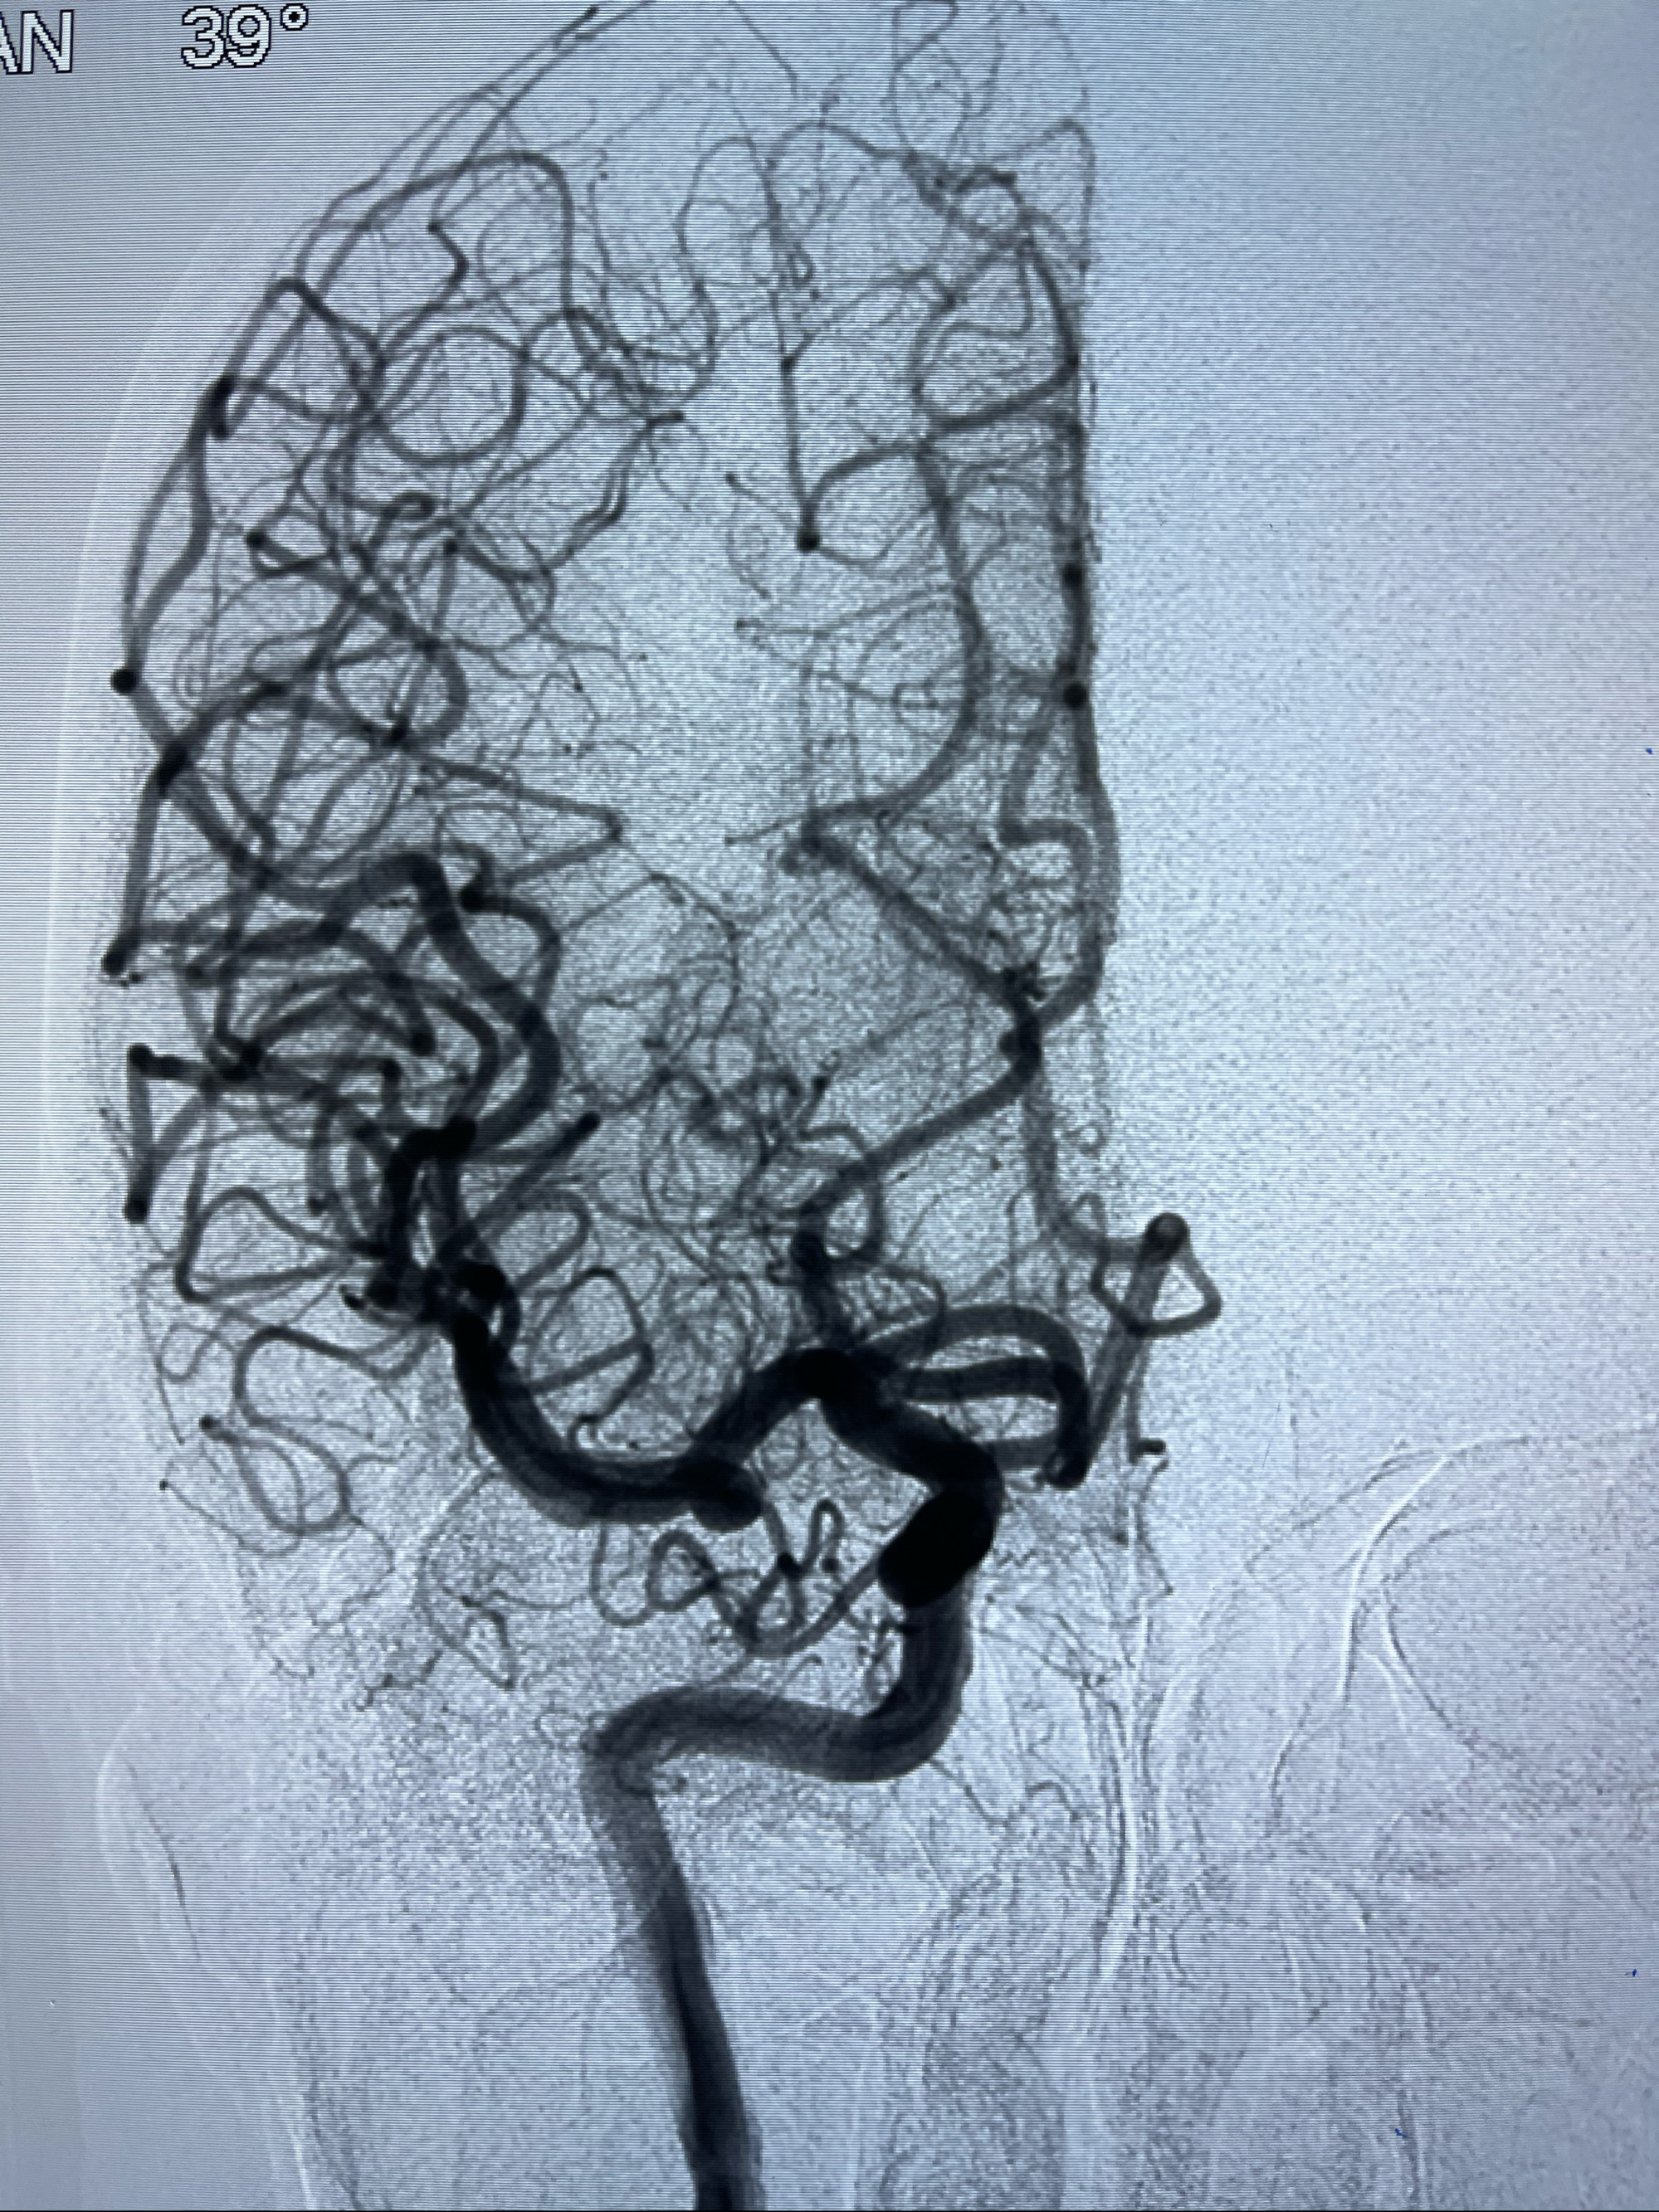

2021-03-08行全脑血管造影

工作角度造影